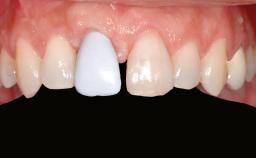

A 45-year-old woman with a completely edentulous maxilla was referred to evaluate the possibility of rehabilitation with an implant-supported prosthesis. This patient was healthy and a non-smoker. She had been wearing a maxillary complete denture opposing a natural mandibular dentition since her twenties. This situation had resulted in progressive resorption of the alveolar ridge, repeatedly creating a need for relining the denture. Twenty years later, despite multiple adaptations and the use of “glues” the denture was unstable and causing the patient psychological and functional discomfort.

Prosthesis Type FDP

Defining Characteristics Fully edentulous upper jaw to be rehabilitated with an implant-borne fixed dental prosthesis